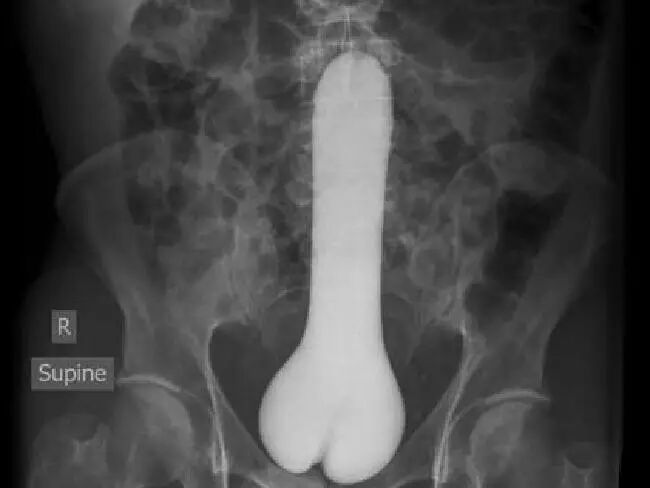

看看急诊来的这些患者,有重要部位直不起来、挫伤、折断的,还有吃了壮阳药重要部位挺立一晚上下不去的,甚至还有尿道和膀胱里进异物的。

▲男子膀胱内异物